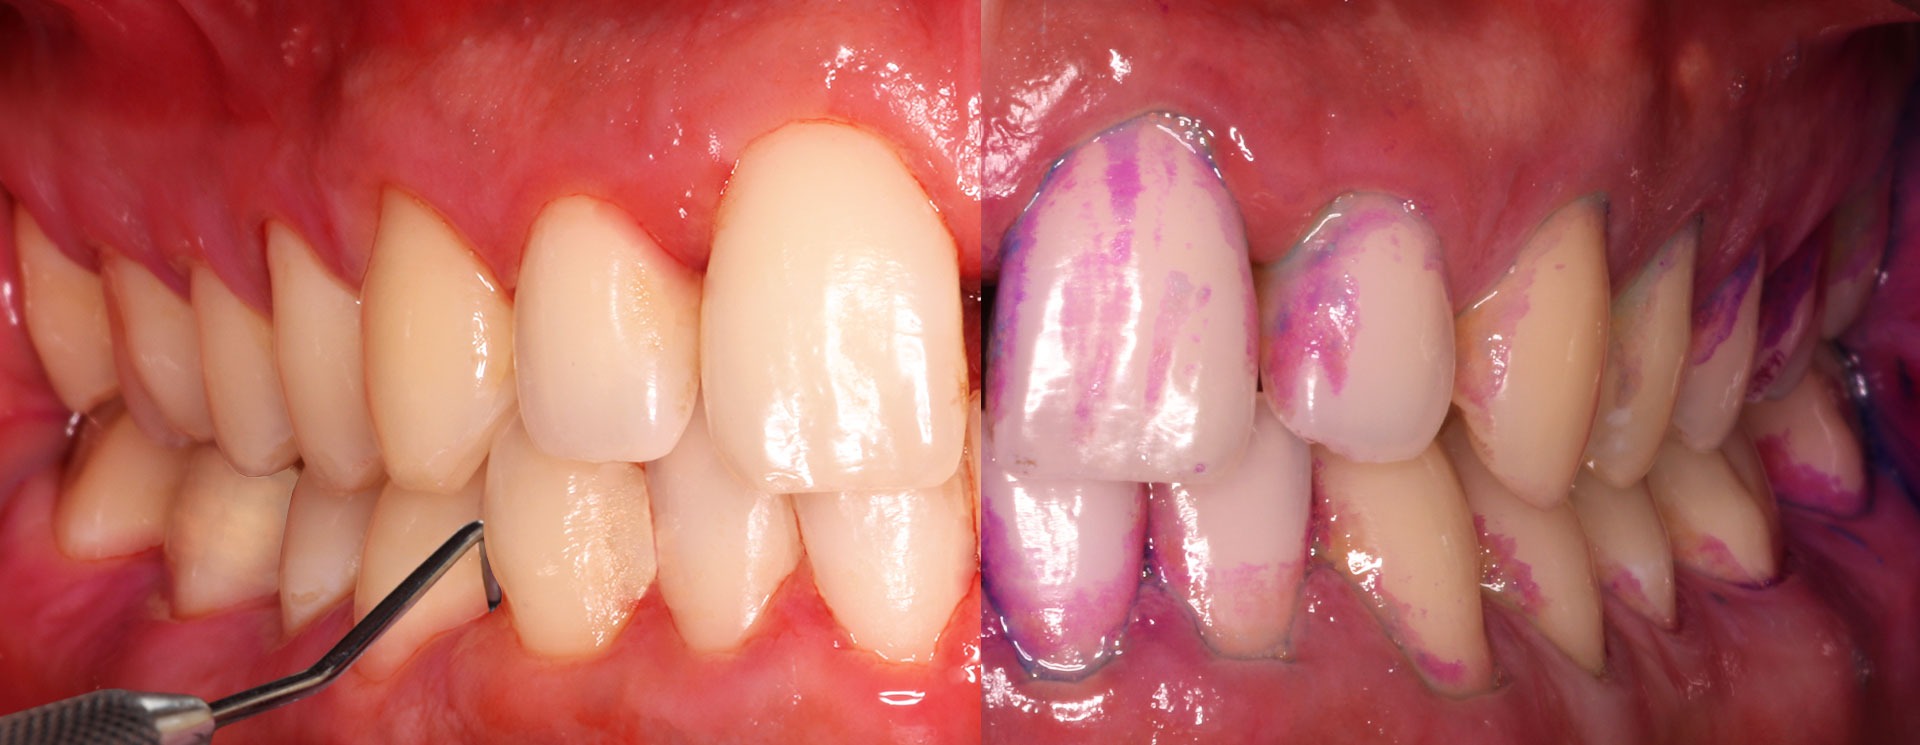

Gengivite